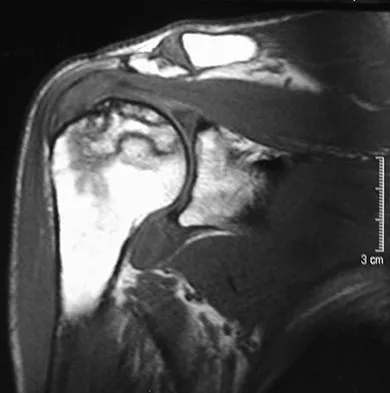

Figures 3a and 3b show the current radiographs of a 58-year-old man who underwent total knee arthroplasty with a cruciate ligament sparing prosthesis 7 years ago. Examination reveals boggy synovitis and moderate pain, particularly anteriorly. Management should consist of

Explanation

The patient has symptoms of synovitis that are most likely the result of the release of particles from the tibial polyethylene. While observation may be warranted in a completely asymtomatic knee, some intervention is indicated for this patient as there is clear radiographic evidence of lysis in both the tibia and femur. The decision about the extent of the revision should be made at the time of surgery. A limited incision technique is not indicated. Grafting (or using graft substitute) the defect is the most appropriate approach for treating the osteolytic lesions. While a posterior stabilized prosthesis might be the solution, surgical findings might dictate otherwise.